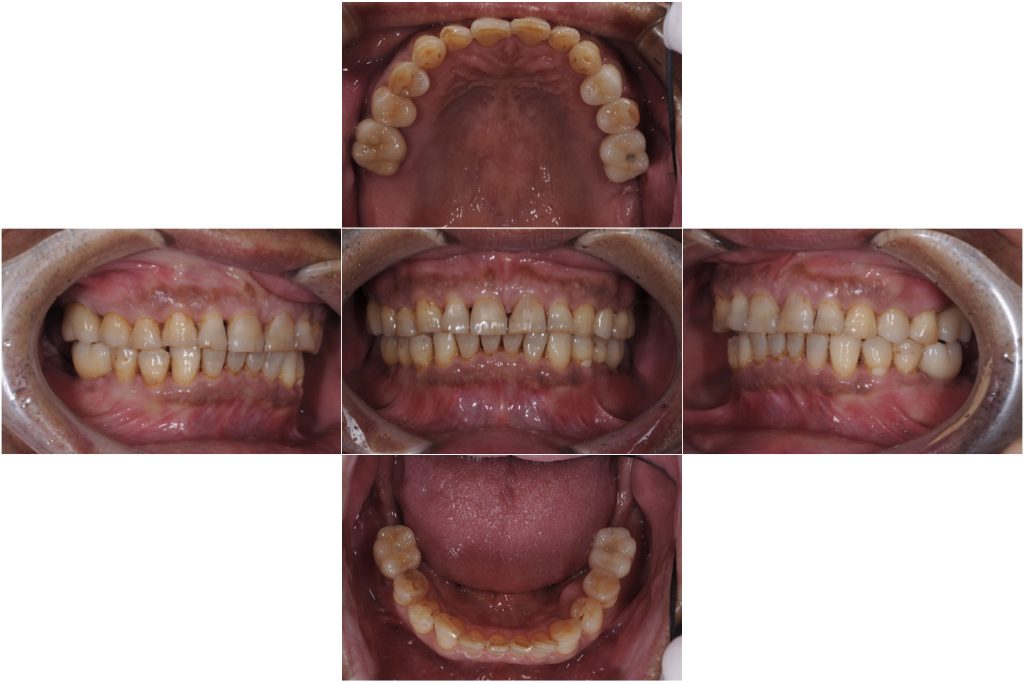

治療内容 ・インプラント

・セラミック修復

治療期間 8ヶ月

治療費用 250万円

天然歯は全体的にかなりすり減りが認められるため、セラミックの材質についても周りの歯の形態に馴染むものを選択した。

抜歯とインプラントのタイミングを計画的に行うことで、治療期間も短く治療を終えることができた。